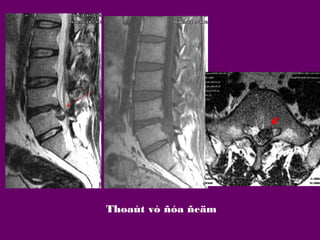

LOAÏI THOAÙT VÒ ÑÓA

ÑEÄM

-Thoaùt vò ñóa ñeäm ra sau

(Posterior DH): Thoaùt vò vaøo

oáng soáng/ thoaùt vò ñóa ñeäm.

Thoaùt

vò

ñóa

Thoaùi hoaù-Thoaùt

vò ñóa ñeäm- Daøy

daây chaèng vaøng-

Thoaùt vò ñóa ñeäm